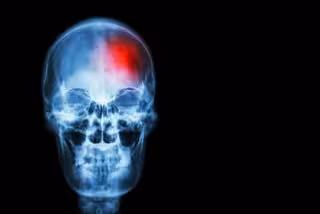

Avances en la terapia endovascular para pacientes con accidente cerebrovascular

Archivo - Ictus